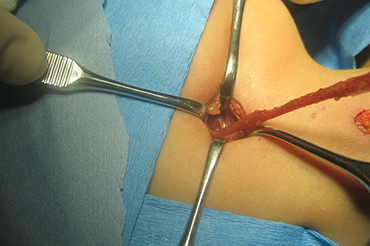

Fistula Branquial